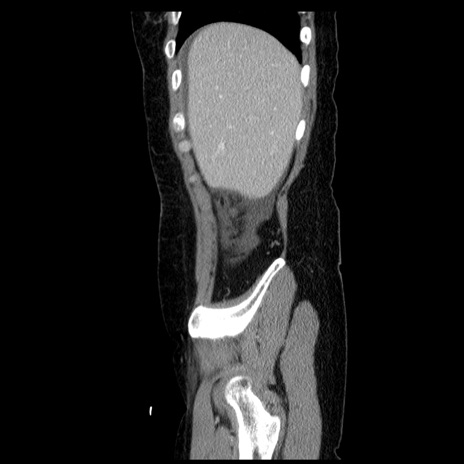

横断像